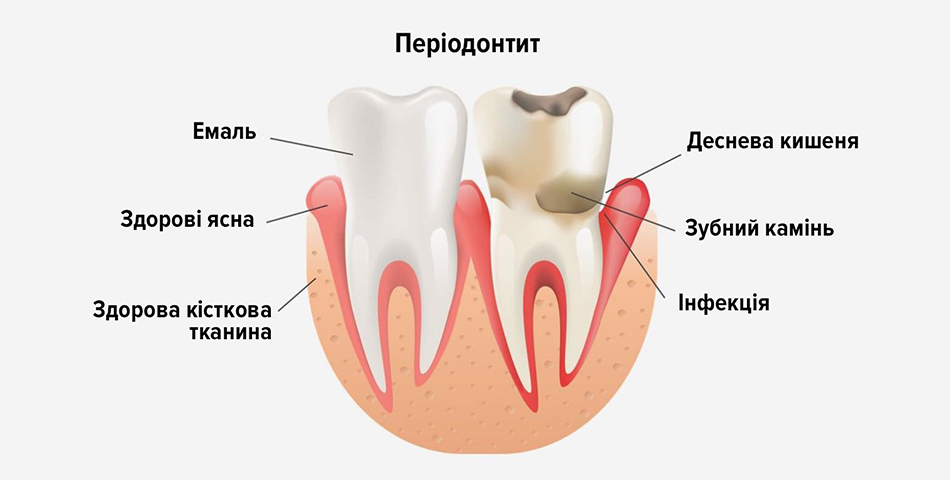

Періодонтит — це серйозне запальне захворювання тканин (періодонту), що оточують корінь зуба та утримують його в кістковій лунці. Його провокує інфекція, яка призводить до розриву зв’язок, поступового руйнування кісткової тканини навколо кореня та кортикальної пластинки. Клінічно це виявляється у вигляді почервоніння і набряку ясен, формування гнійного вогнища (абсцесу) під коренем зуба та сильного, часто пульсуючого болю, що посилюється при накушуванні.

Розвиток захворювання завжди пов’язаний з проникненням патогенної мікрофлори в простір навколо верхівки кореня. Основні причини:

- Глибокий карієс, що перейшов у пульпіт, коли інфекція з камері пульпи поширюється через кореневі канали далі.

- Неякісне попереднє пломбування кореневих каналів, коли вони оброблені не на всю довжину або заповнені неплотно, що залишає простір для розмноження бактерій.